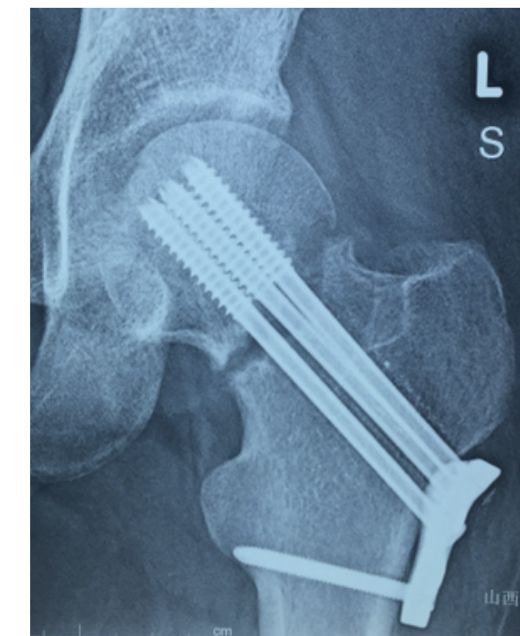

• 股骨近端骨折禁止应用钢板

此处应用钢板有两种情况一是不会使用髓内固定,设备条件达不到;再就是理念落后见的病例少,交流少。此处外侧全部是长应力,钢板为张力钢板,内收肌力量强大,目前的钢板不能承受反复的弯曲应力,金属疲劳断裂失败率高,以下病例切开,钢丝捆绑进一步骨膜剥离,破坏了原始血肿,干扰骨愈合,都是失败原因